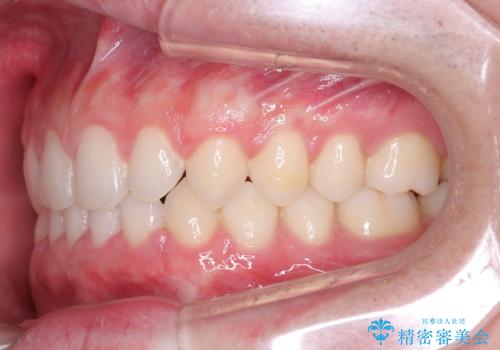

- 主訴:上の歯列の空隙を閉じたい

上顎前歯部に空隙が目立ちました。ワイヤー矯正、インビザライン(マウスピース矯正)どちらの方法でも適用症例と説明し、ワイヤー矯正治療(審美装置)を希望されました。

上顎歯列の空隙を閉じるのと一緒に、ディープバイト気味の被蓋も下顎前歯の圧下を行い改善しました。